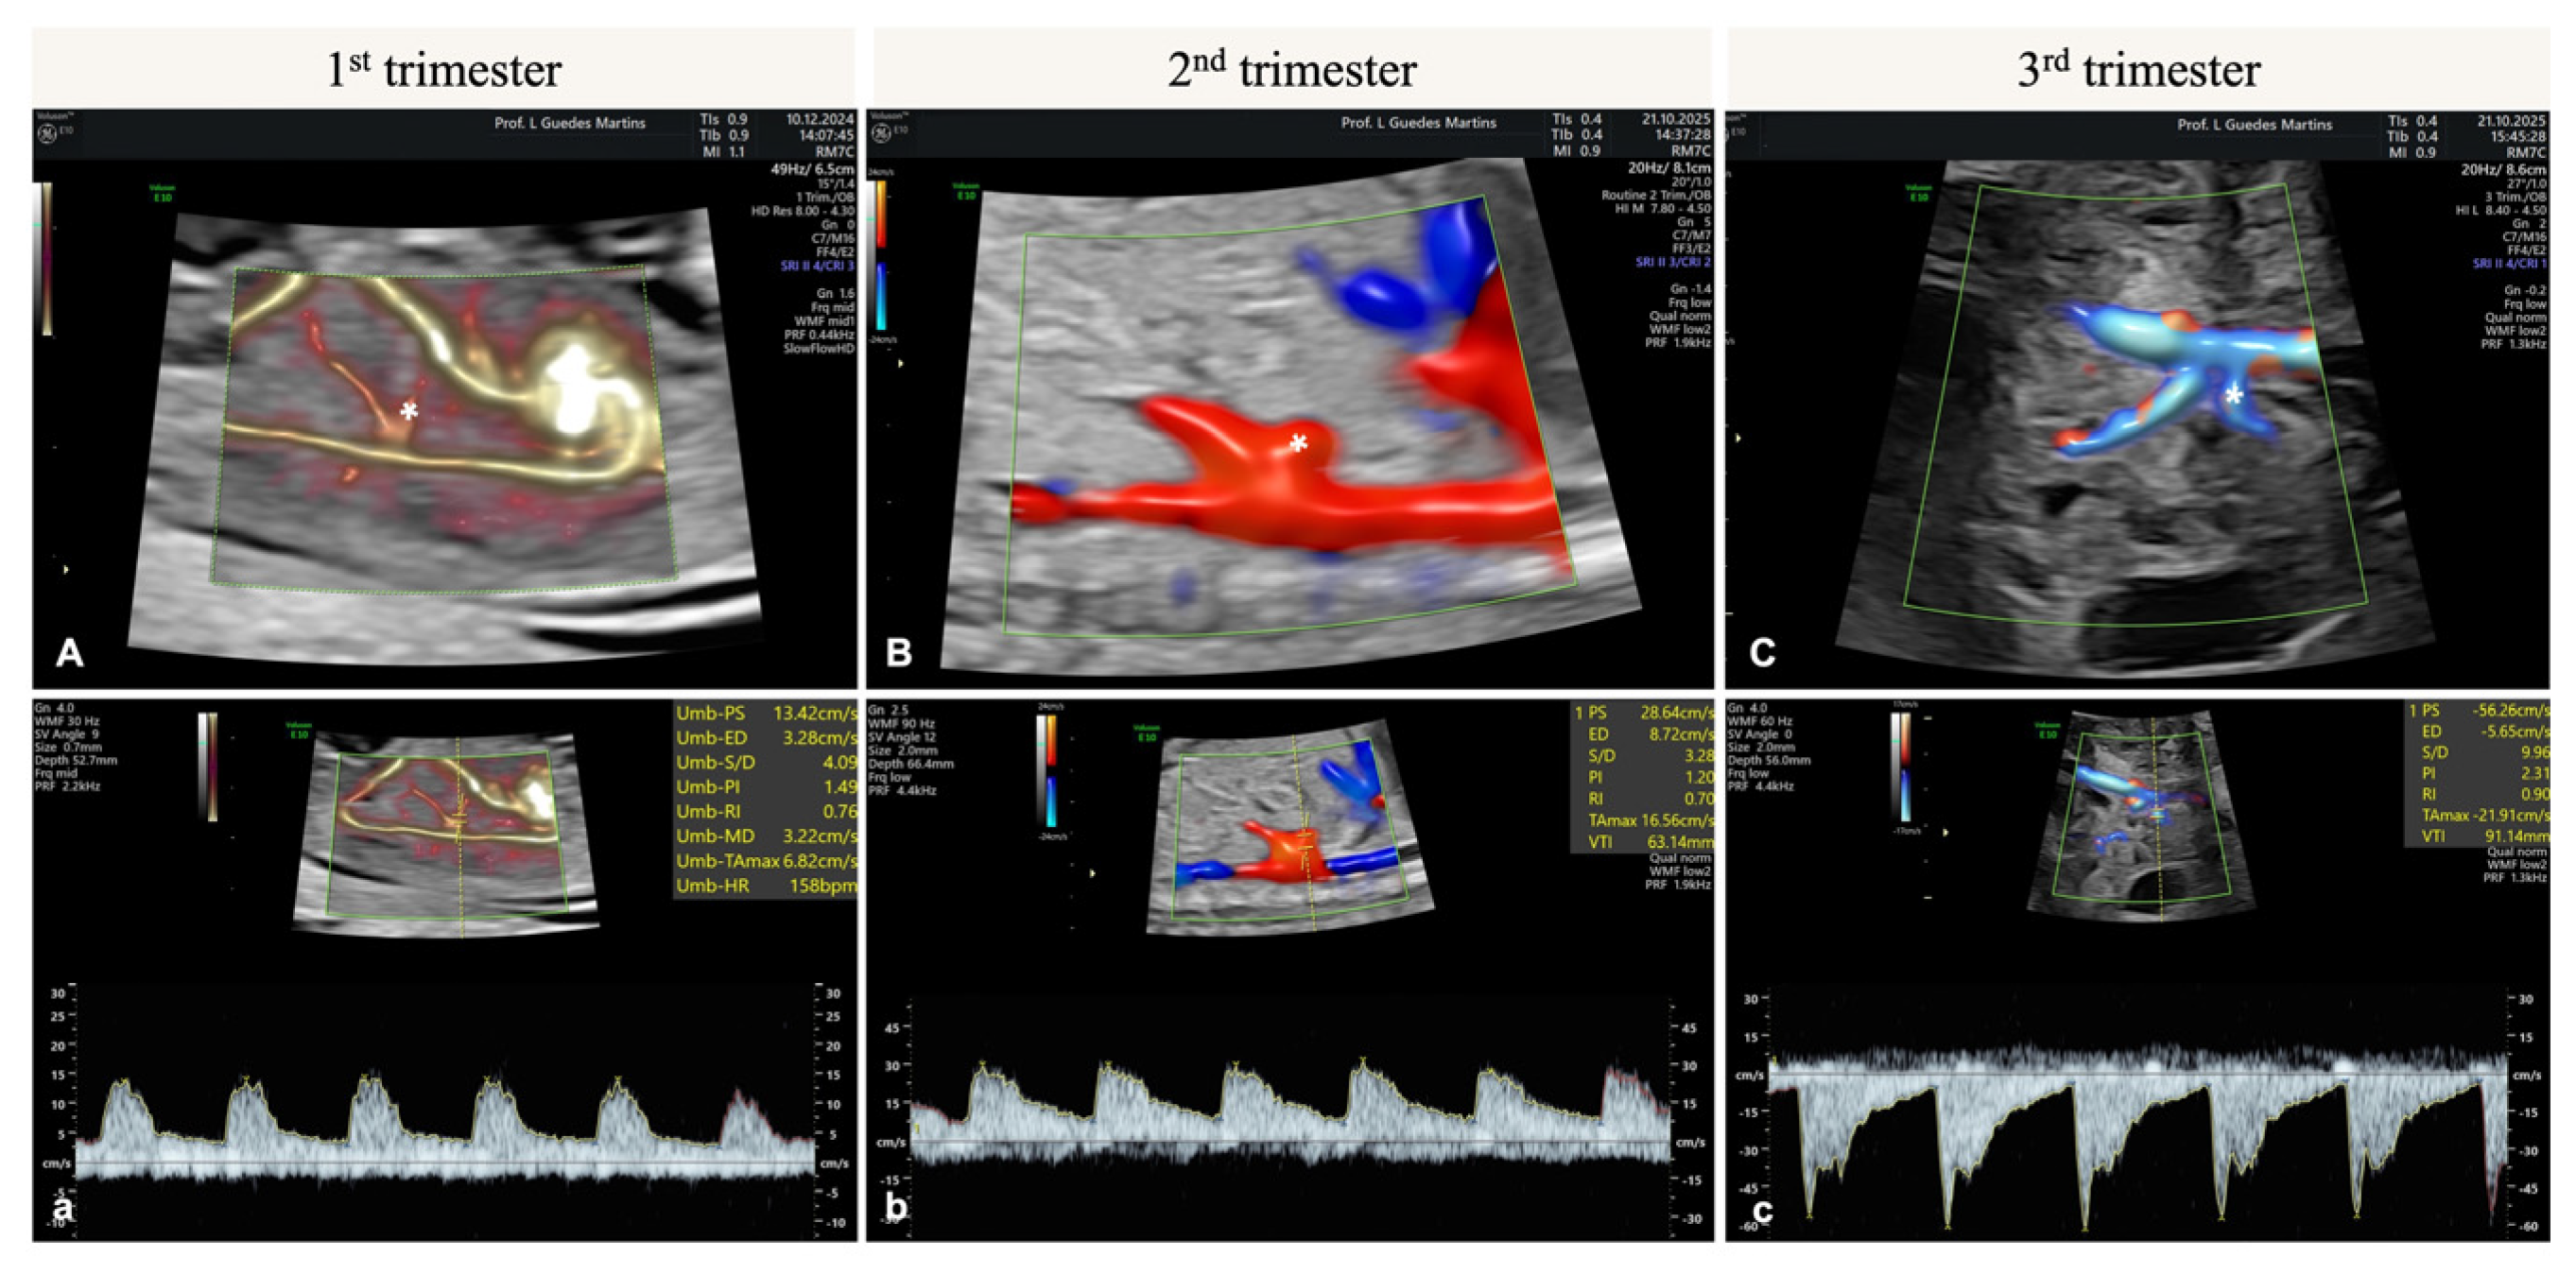

7. Hepatic Artery Doppler